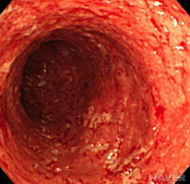

궤양성대장염 완치 약 정보 공유

#궤양성대장염 #궤양성대장염완치 #궤양성대장염약 #궤양성대장염정보 #궤양성대장염공유 #궤양성대장염원...